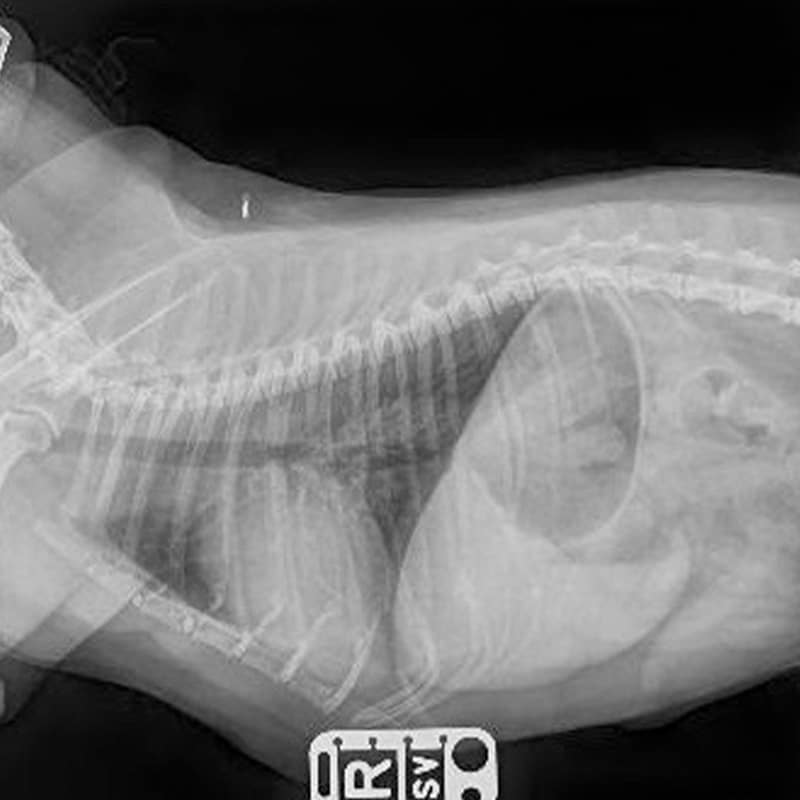

Digital X‑Ray

Our digital radiography system produces crisp images of bones and dense tissues in seconds. It’s ideal for diagnosing fractures, arthritis and other orthopedic issues, and digital files can be shared instantly with specialists for consultation.